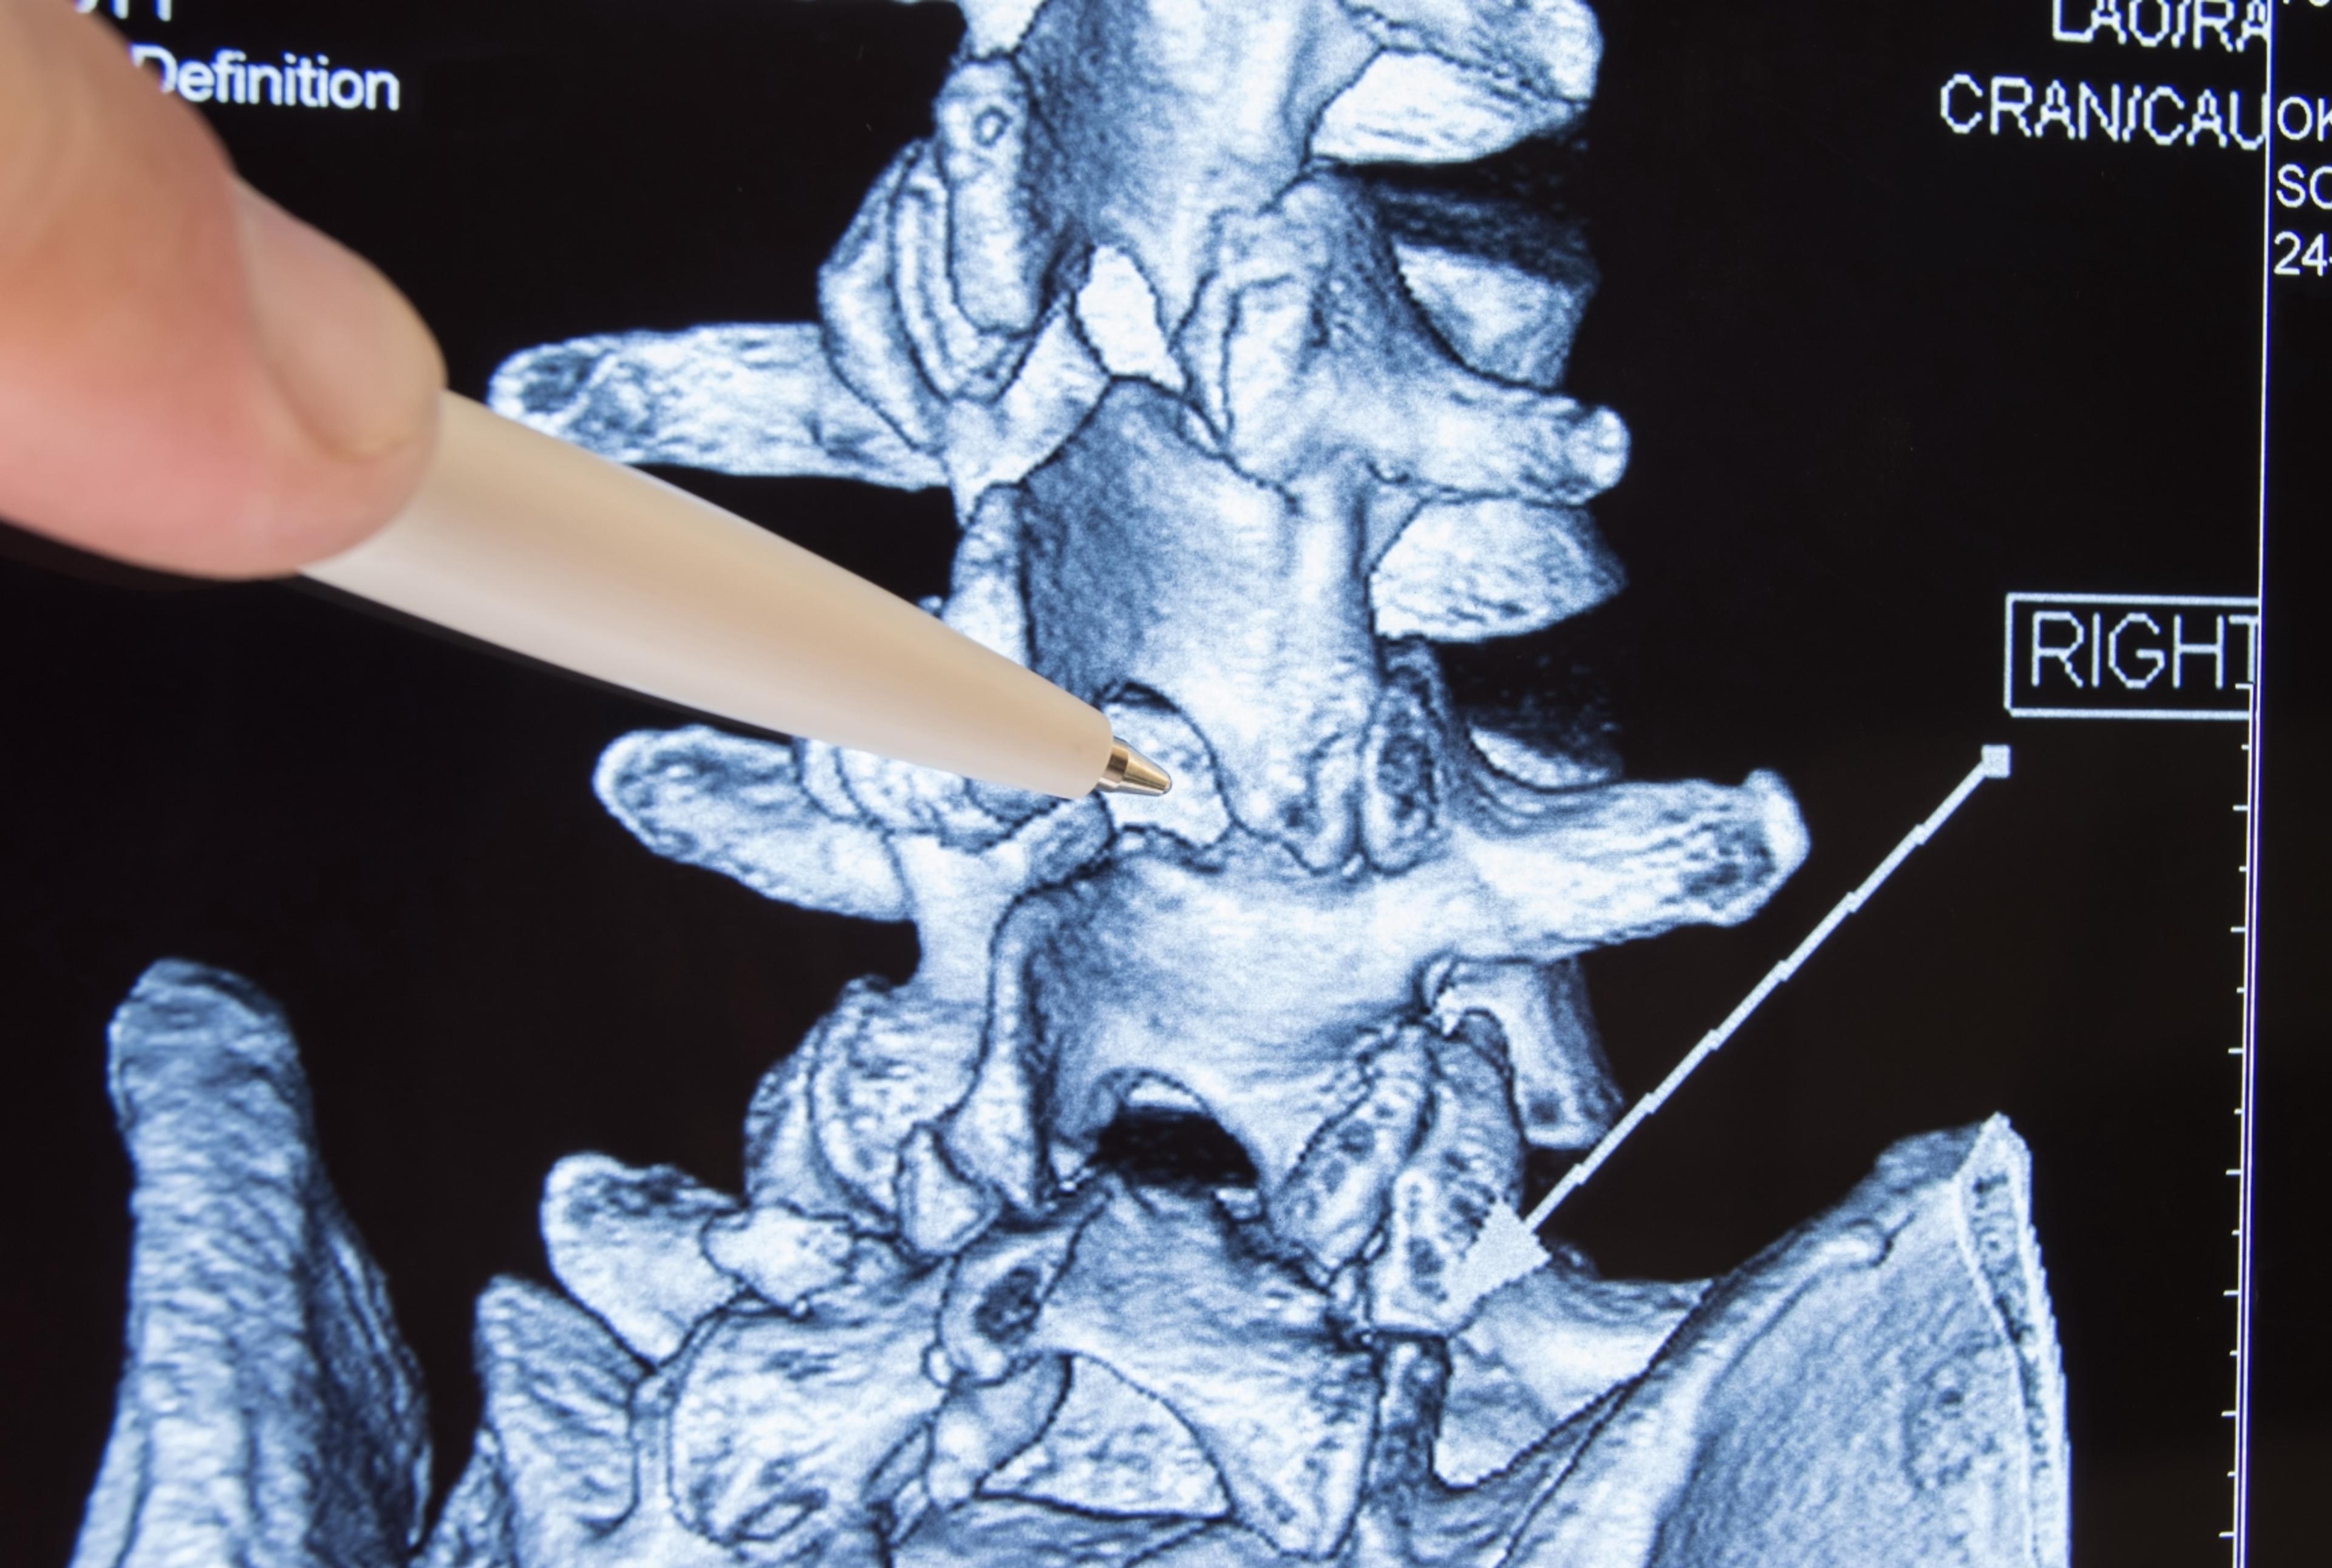

- Vertebroplasty

Vertebroplasty helps treat the pain and stabilize vertebral compression fractures. A relatively new procedure done on an outpatient basis, it involves making a small incision in the skin while using image guidance to insert a needle filled with a specially formulated acrylic bone cement into the vertebra.